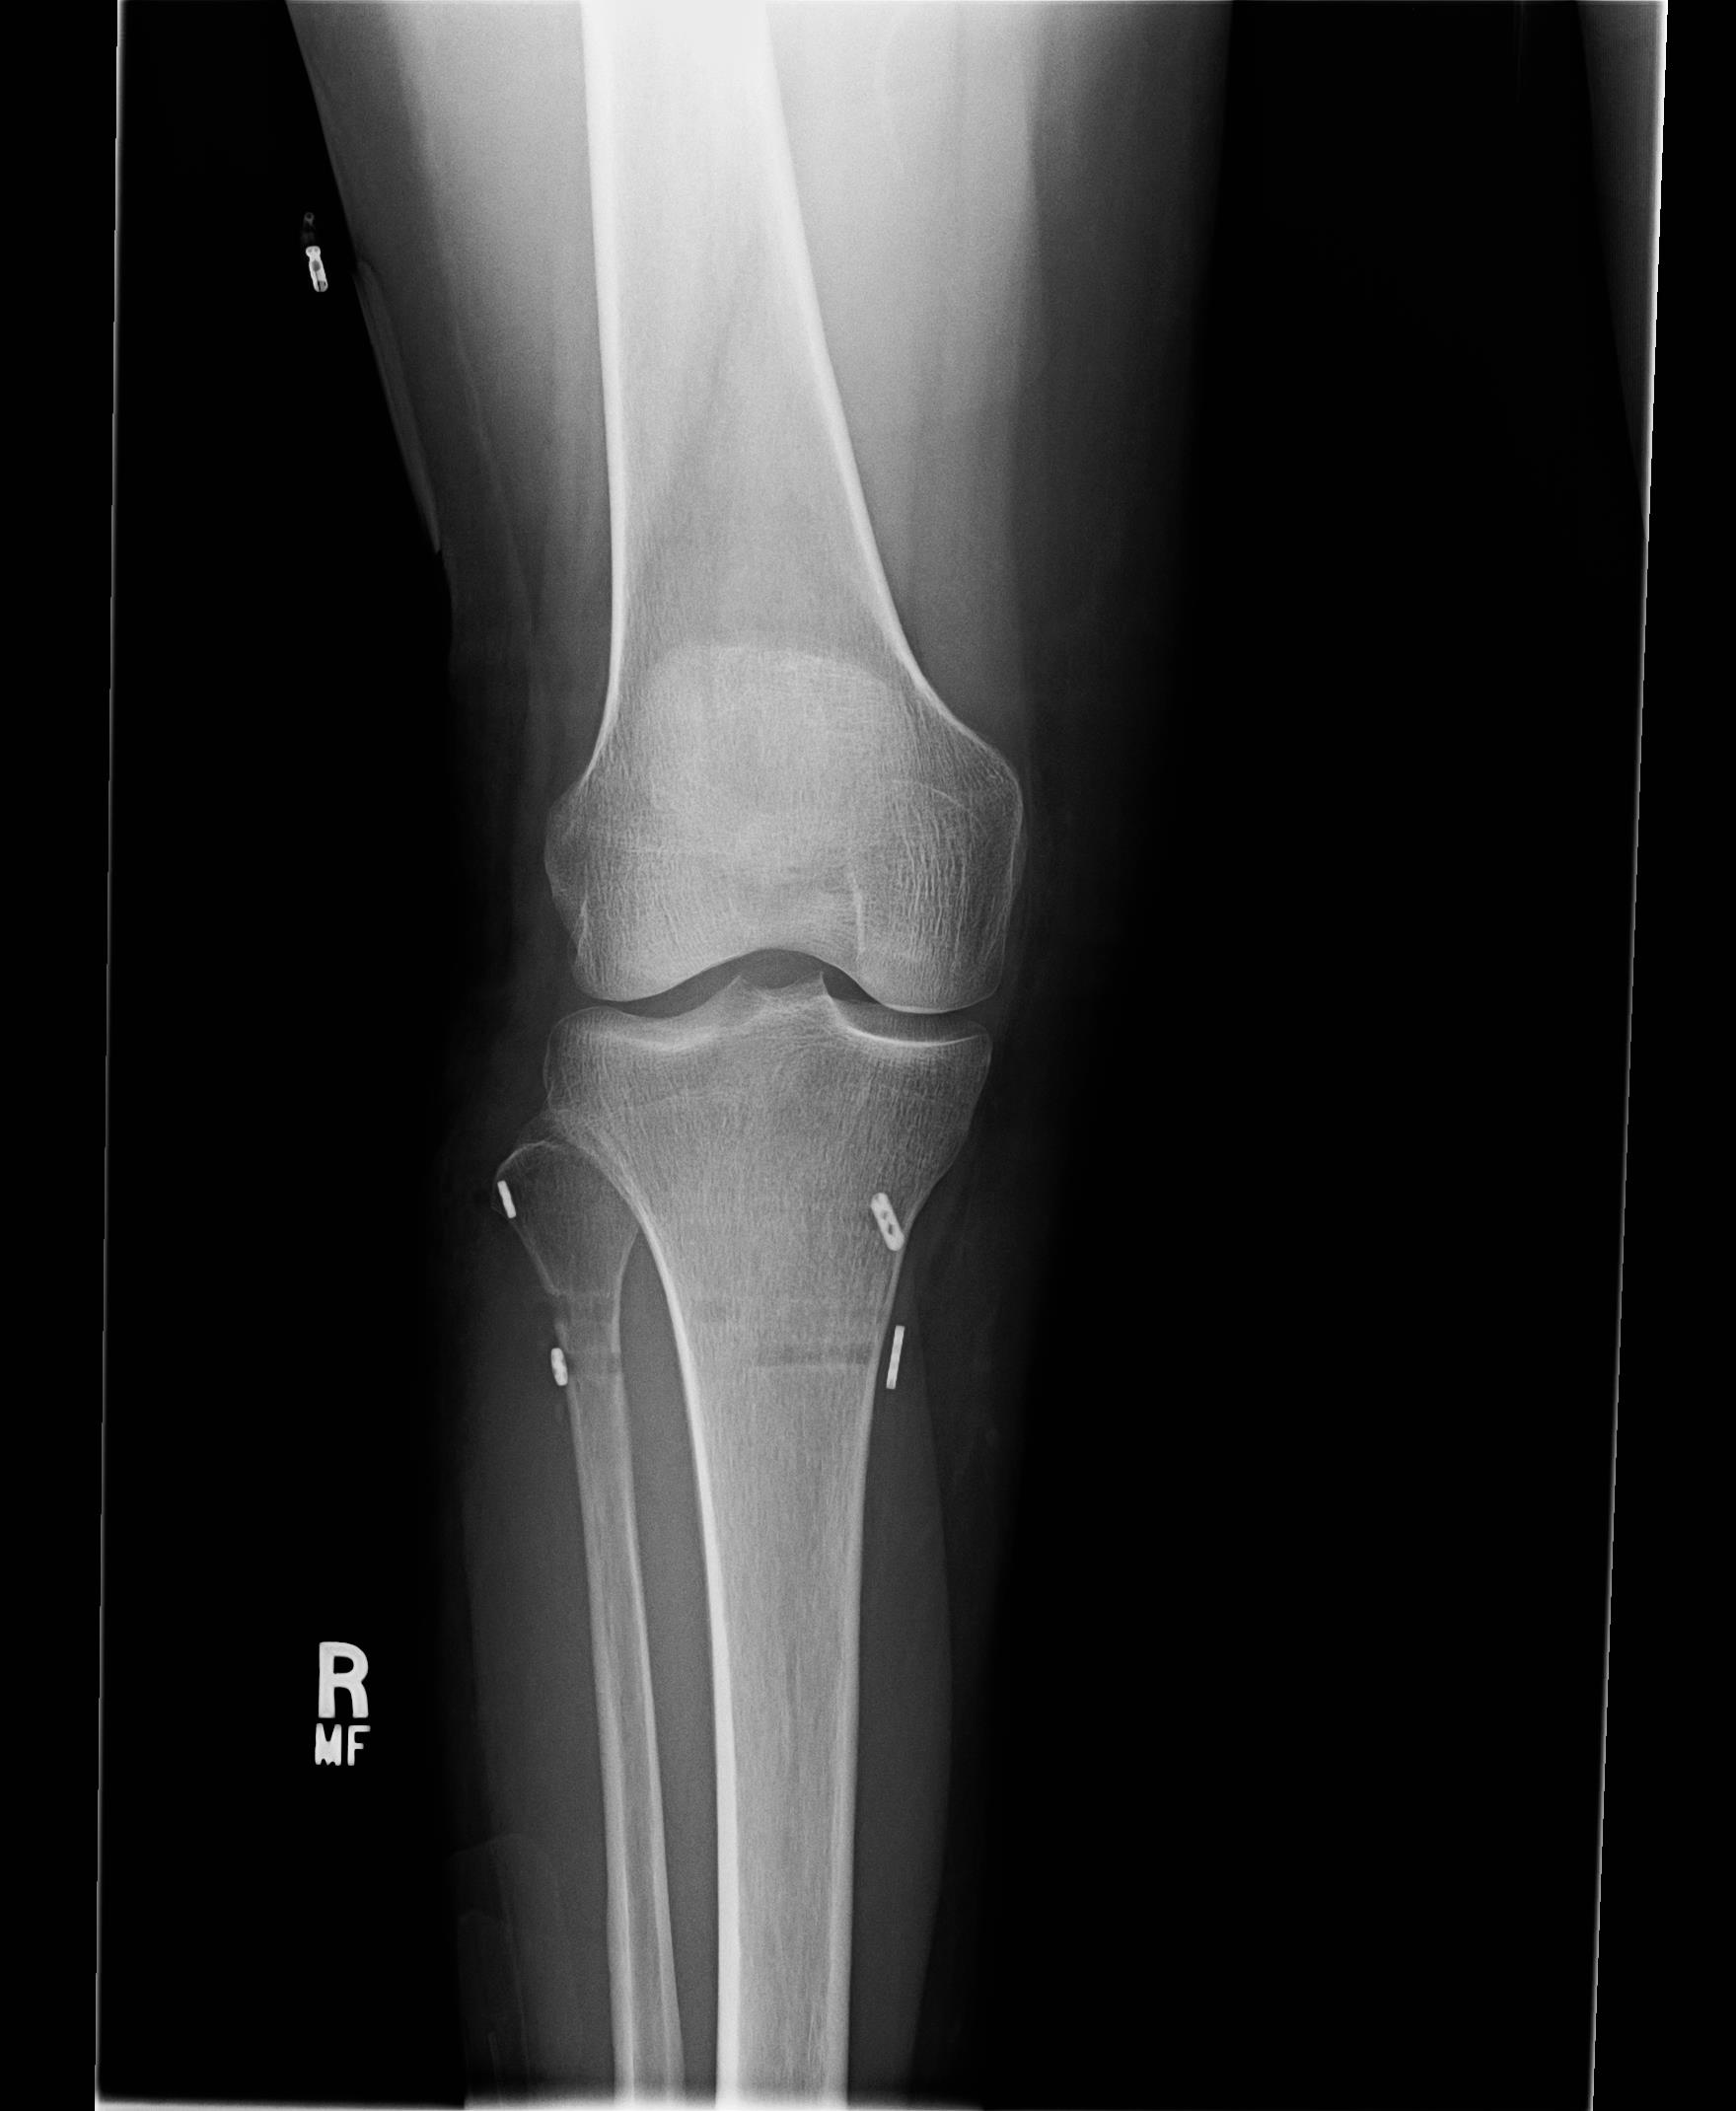

Post surgical X-rays are shown farther down in this blog. For those readers that want the surgical procedure details, please click each link for the PDF pages of the surgical report:

2. Dr. Main and I had discussed my right ankle joint still having some slight pronation and pain around the distal tib-fib. During surgery after doing the proximal fixations and tightening of the proximal syndesmosis, he checked the distal syndesmosis and it still showed some slight instability. He therefore went ahead and placed another Arthrex TightRope Fixation into the distal tib-fib of the ankle. All the fixations can be seen in the X-rays below in this blog.

Monday, 3-31-14— First Follow up appointment at 4 days since surgery. Post surgical x-rays taken of my right lower leg and ankle at Dr. Main’s office (click on photos to enlarge):